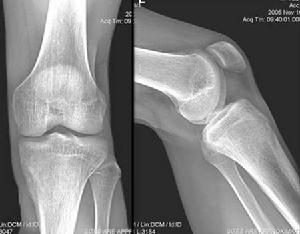

【每周读片】骨样骨瘤

700x271 - 21KB - JPEG